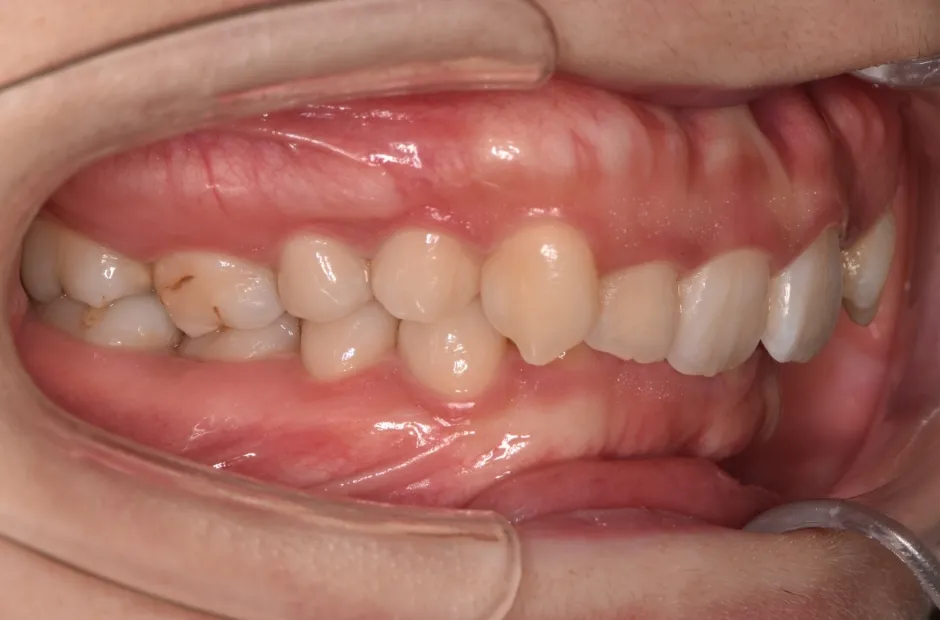

叢生

| 診断名・主訴 | 叢生 |

|---|---|

| 年齢・性別 | 43歳・女性 |

| 治療期間・回数 | 2年7か月 27回 |

| 治療に用いた主な装置 | 舌側矯正 |

| 抜歯部位 | 両顎4,4 |

| 治療費 | 100万円(税抜) |

| リスク・副作用 | 装置による違和感・疼痛・歯肉退縮・歯根吸収・虫歯のリスクなど |